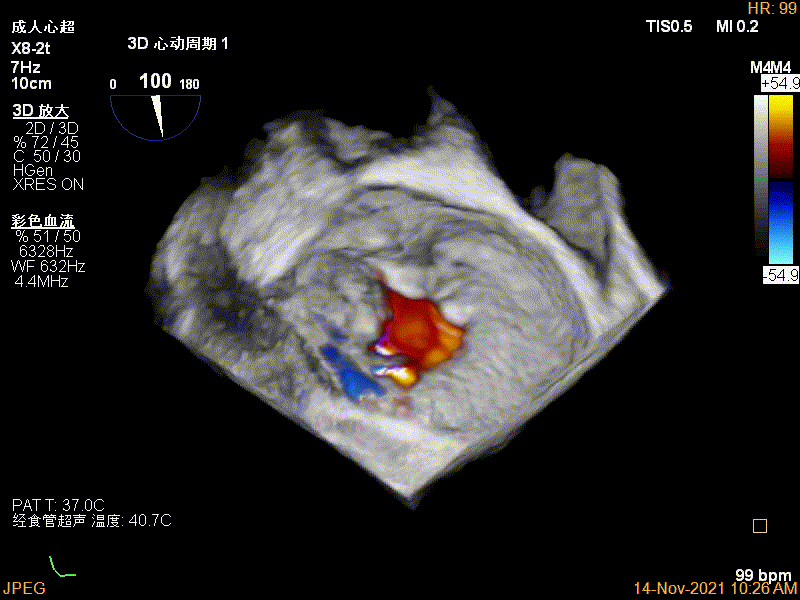

3D-color视图下两个夹子间少量残余反流

肺静脉血流频谱恢复正向

二尖瓣瓣口平均跨瓣压差:3mmHg